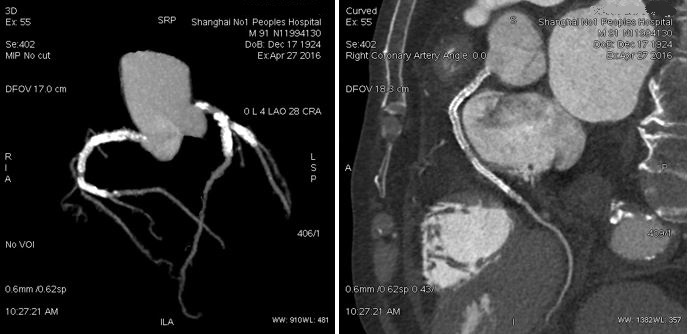

患者男性,91岁。PCI术后,心率57-233BPM,患者心律失常,因年老不能配合呼吸控制,Revolution冠脉检查采用自由呼吸。